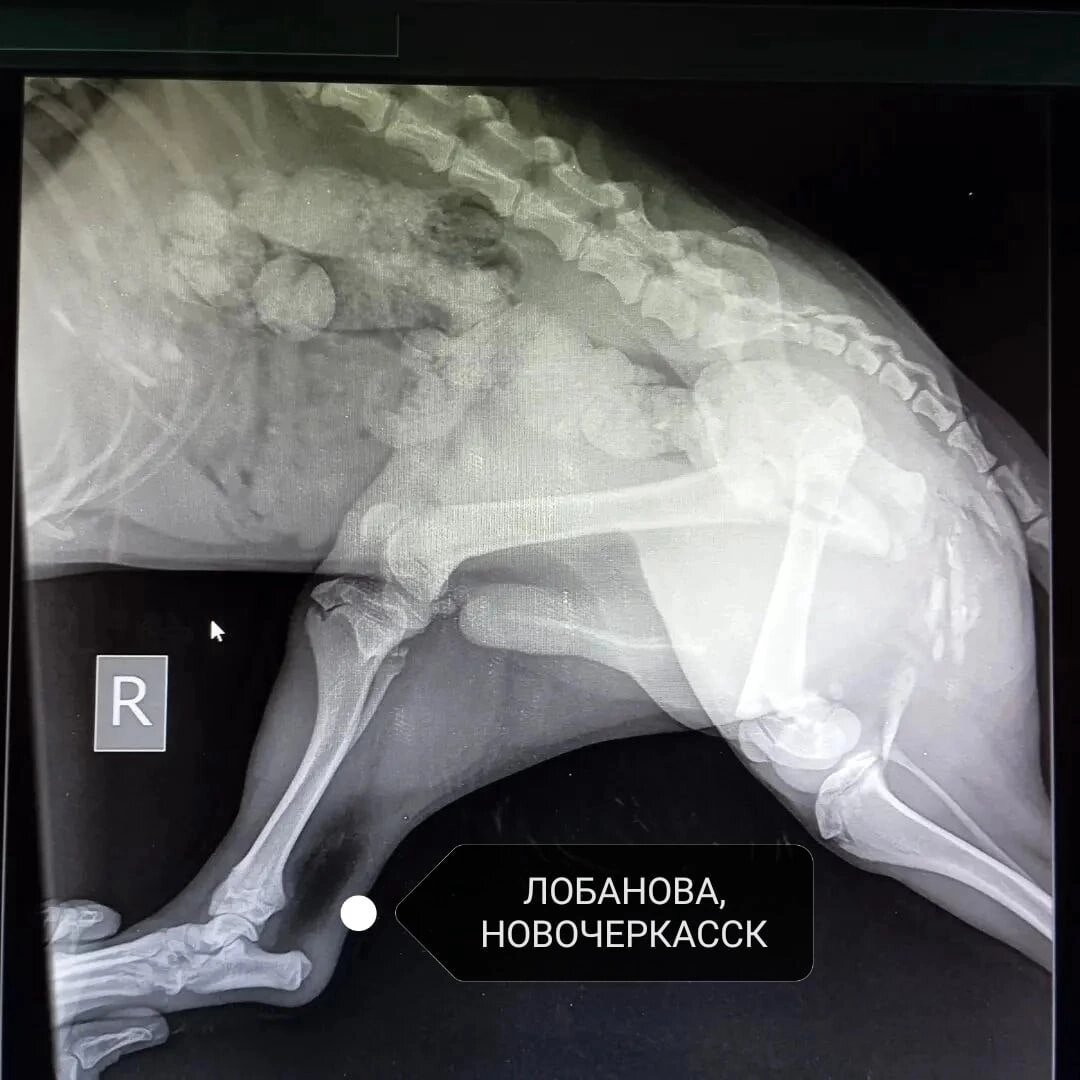

Сразу отвезли в клинику Вета на Александровской, прием вела Татьяна Анатольевна. По рентгену множественные переломы обеих задних лап в области бедер. Операцию решено было не проводить, а оставить на месяц в ограниченном пространстве для естественного сращивания костей.

Было решено показать его хирургу - ортопеду. Консультирование проводил доктор Чуняеа Андрей Александрович в клинике "Толстый Лори" на Бестужевской 10. Был сделан рентген обеих задних лап, который показал смещение суставов в результате неправельного сращивание костей после перелома. Доктор рекомендовал оперировать (Резекционная артропластика тазобедренного сустава)

При переломе косточки сраслись, но не правильно (операцию не делали) и тем самым произошло смещение суставов.